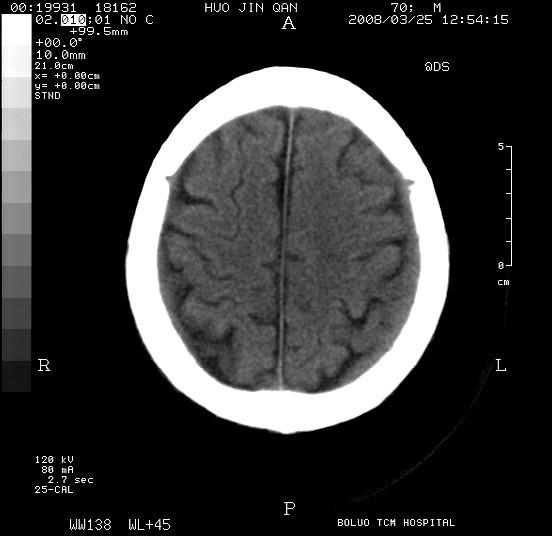

以下是引用随光逐影在2008-3-25 20:15:00的发言:[br]双侧额颞顶部亚急性(或慢性)硬膜下血肿。

以下是引用liuyue在2008-3-26 18:57:00的发言:[br]以下是引用随光逐影在2008-3-25 20:15:00的发言:[br]双侧额颞顶部亚急性(或慢性)硬膜下血肿。 [br]支持![br]可以无明显外伤病史,老年人可以在激烈摇晃或轻微头部碰创头部时,发生硬膜下出血.